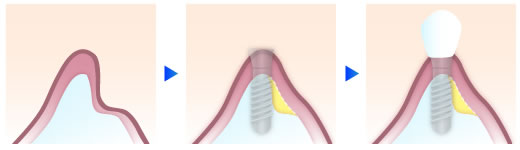

ソケットリフト

上顎にインプラントを埋入する際に、骨の厚みが5mm以上と比較的厚みがある場合には、埋入する穴から人工骨で押し上げる事で、埋入に必要な骨の厚みを獲得する方法です。